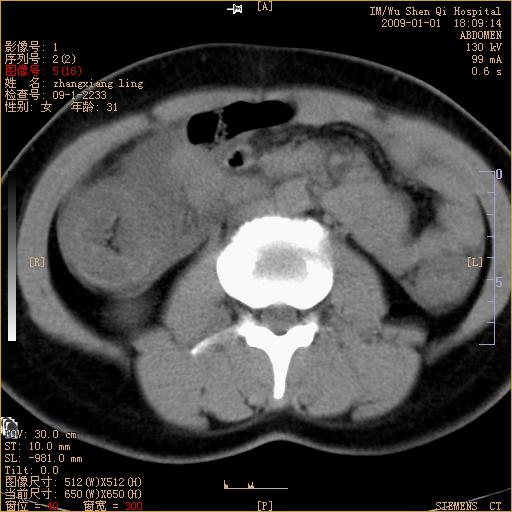

标题: CT17527:F31Y,腹痛伴血便9小时 [打印本页]

标题: CT17527:F31Y,腹痛伴血便9小时

升结肠肠壁不规则增厚,肠腔狭窄,考虑升结肠占位,建议增强扫描

升结肠肠壁不规则增厚,肠腔狭窄,考虑升结肠占位,建议增强扫描,不除外肠套叠.

升结肠肠壁不规则增厚,似呈同心圆改变,其有积液。结合病史首先考虑肠套叠伴肠壁坏死可能性大,结肠肿瘤待排。

升结肠肠壁不规则增厚,似呈同心圆改变,其有积液。结合病史首先考虑肠套叠伴肠壁坏死可能性大,结肠肿瘤待排。支持!(发病急,无过去史,应首先考虑:肠套叠)

患者已手术,结果肠系膜血栓形成肠坏死

患者已手术,结果肠系膜血栓形成肠坏死。

结合病史并看到升结肠增粗及局限的腹腔积液,考虑肠套叠伴肠壁坏死可能性大

结果:患者已手术,结果肠系膜血栓形成肠坏死。回过头再看局部肠壁增厚有分层(高密度坏死及低密度水肿)表现。